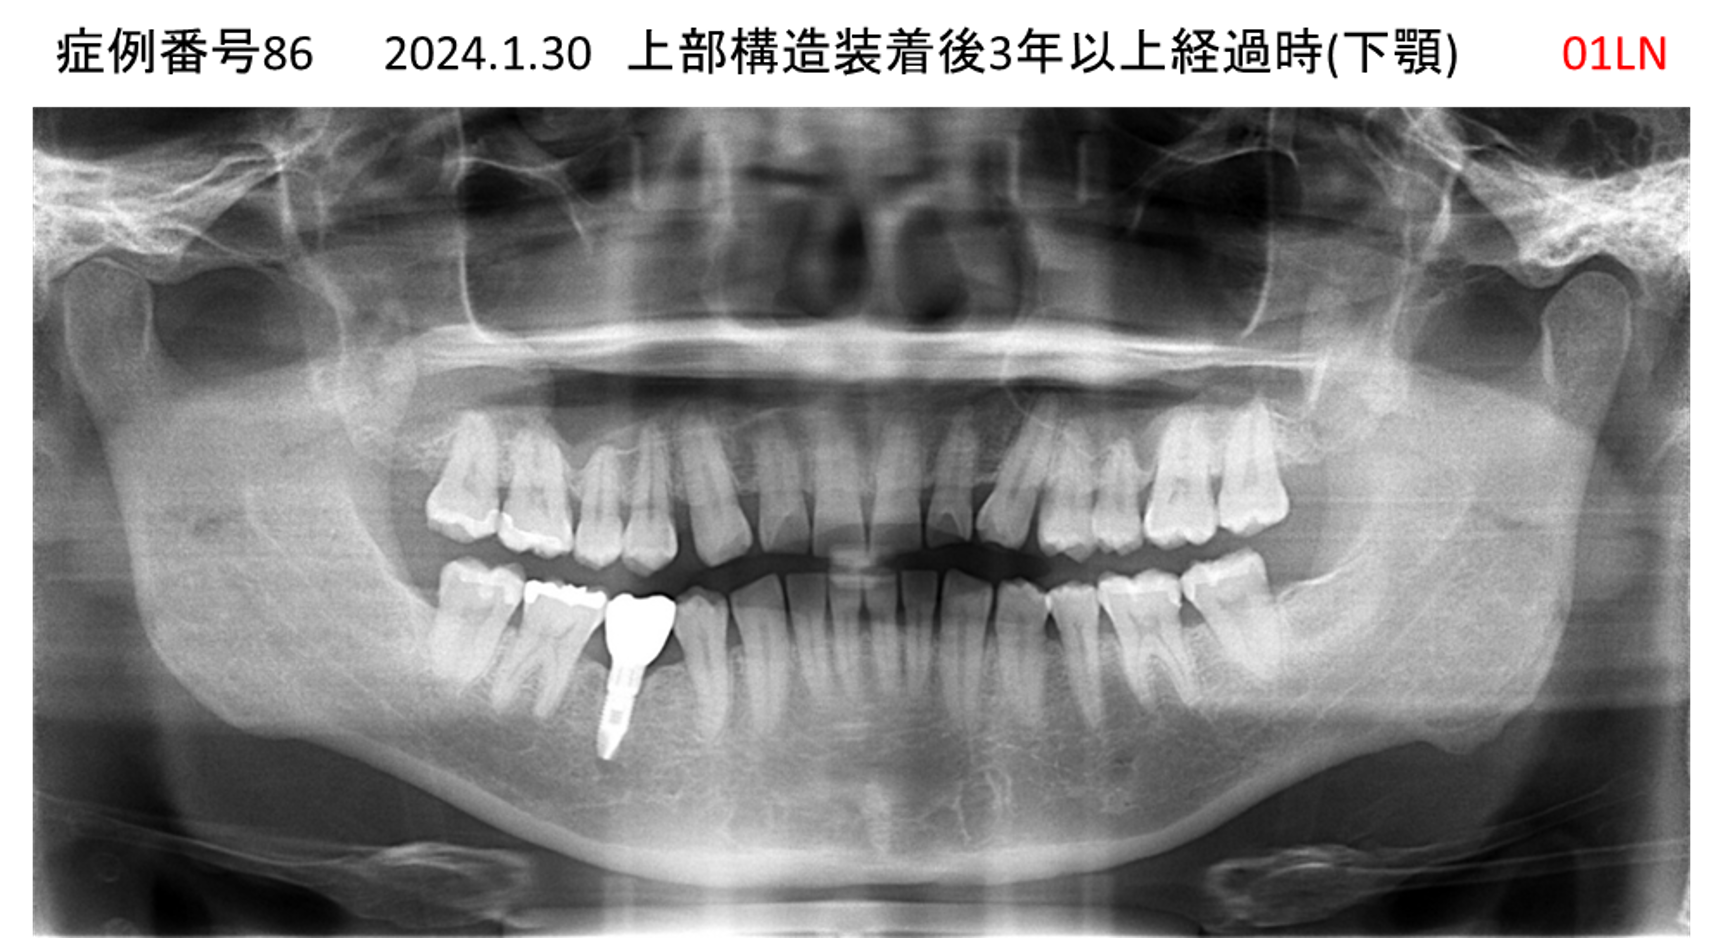

左下の奥歯が痛い患者様のインプラント症例

| 治療名称 |

インプラント |

| 治療費用 |

215万円+税 |

| 治療期間 |

5か月 |

| 患者さんの症状(主訴) |

左下の奥歯が痛い。 |

| 治療内容 |

| 治療結果 |

痛み無く、噛める。 |

| 治療の注意点(リスク/副作用) |

インプラントが壊れたら再治療が必要 |